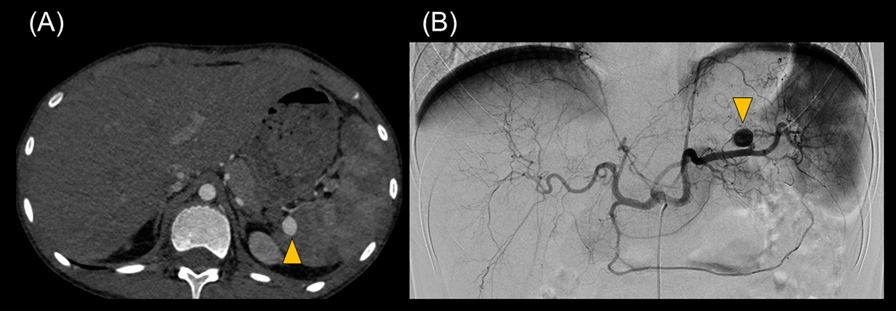

One month after the operation, we repeated the abdominal contrast-enhanced CT scan to follow up renal and splenic infarctions. At this time, we unexpectedly detected a splenic artery aneurysm that was 10 mm in size. Semi-urgent percutaneous coil embolization was carried out using a catheter to avoid aneurysm rupture (Fig. 4). Radiologists approached the SAA using microcatheters, Sniper 2 high-flow type (Terumo, Tokyo, Japan), and MARVEL (Tokai Medical Products, Kasugai, Japan) through a C2 catheter of 4-French (Medikit, Tokyo, Japan) at his celiac trunk. The distal and the proximal portions of the aneurysm were occluded by several coils using Target XL (Stryker Neurovascular, Fremont, CA, US) and C-stopper of 0.014 inch (PIOLAX, Kanagawa, Japan) (Fig. 5). No aneurysm rupture occurred, nor recurrence of IE after embolization.

Fig. 4 (A) Abdominal contrast-enhanced CT and (B) arteriography show the splenic artery aneurysm (arrow head)

Journal of Pediatric Cardiology and Cardiac Surgery 7(2): 63-68 (2023)

Fig. 5 Arteriography shows (A) the splenic artery aneurysm and (B) its coil embolization (arrow head)